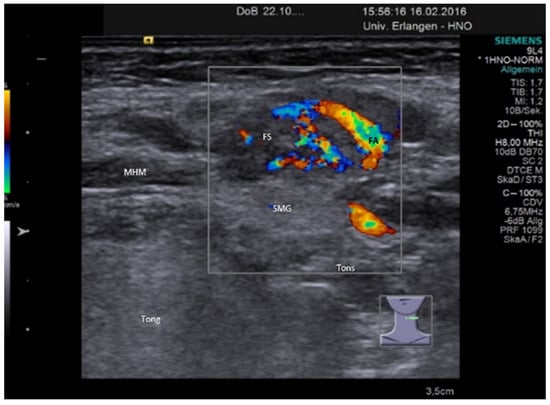

3.3.2. Obstructive Sialadenitis Caused by Sialolithiasis

3.3.3. Non-Sialolithiasis-Caused Unspecific Sialadenitis with Sialodochitis and/or Duct Stenosis with Primary or Secondary Obstruction